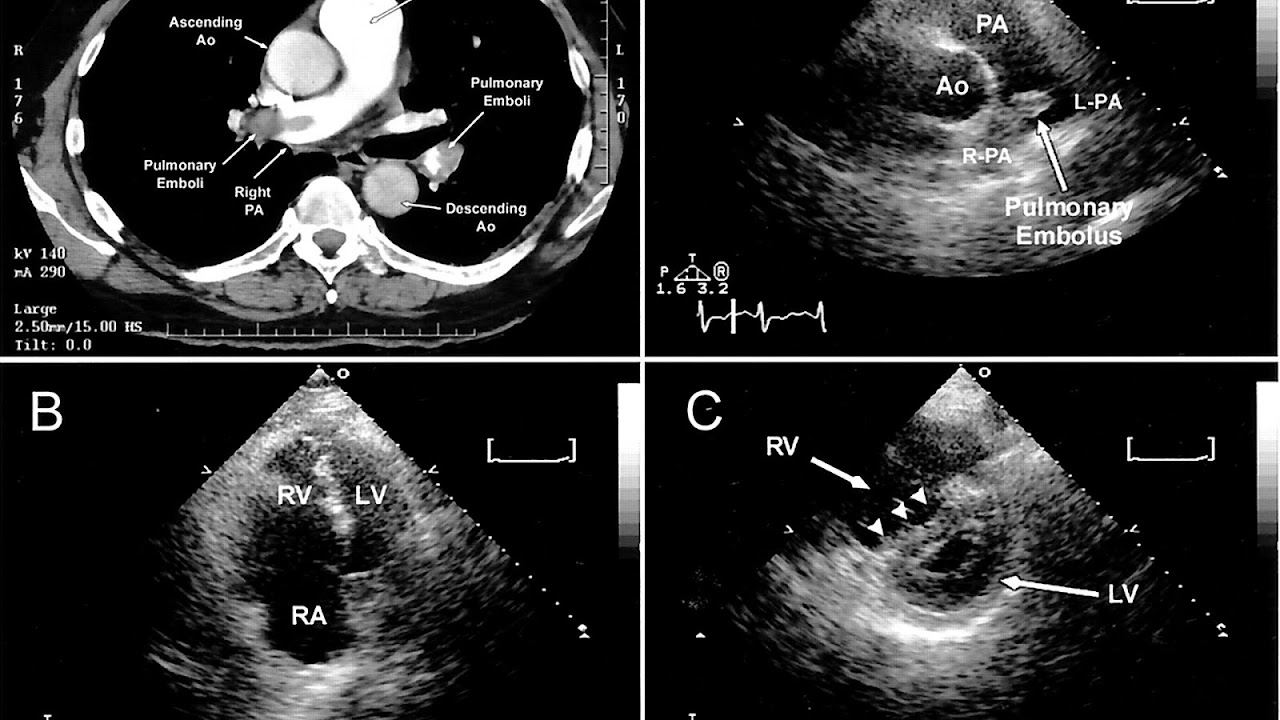

CT pulmonary angiography

CT pulmonary angiography (CTPA) is a pulmonary angiogram obtained using computed tomography (CT) with radiocontrast rather than right heart catheterization. Its advantages are clinical equivalence, its non-invasive nature, its greater availability to people, and the possibility of identifying other lung disorders from the differential diagnosis in case there is no pulmonary embolism.

Echocardiography

In massive and submassive PE, dysfunction of the right side of the heart may be seen on echocardiography, an indication that the pulmonary artery is severely obstructed and the right ventricle, a low-pressure pump, is unable to match the pressure. Some studies (see below) suggest that this finding may be an indication for thrombolysis. Not every person with a (suspected) pulmonary embolism requires an echocardiogram, but elevations in cardiac troponins or brain natriuretic peptide may indicate heart strain and warrant an echocardiogram, and be important in prognosis.

The specific appearance of the right ventricle on echocardiography is referred to as the McConnell's sign. This is the finding of akinesia of the mid-free wall but a normal motion of the apex. This phenomenon has a 77% sensitivity and a 94% specificity for the diagnosis of acute pulmonary embolism in the setting of right ventricular dysfunction.